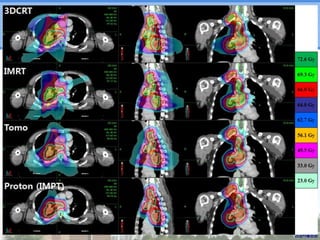

Dose-volume Histogram (DVH) 100 ProtonPTV 90 Proton Spinal Cord Normalized volume (%) 80 Proton Both Lungs 70 IMRT PTV IMRT Spinal Cord 60 IMRT Both Lungs 50 3DCRT PTV 40 3DCRT Spinal Cord 30 3DCRT Both Lungs Tomo PTV 20 Tomo Spinal Cord 10 Tomo Both Lungs 0 0 10 20 30 40 50 Dose (Gy) 60 70 80

Dose-volume Histogram (DVH)

100

Proton PTV

90

Proton Spinal Cord

Normalized volume (%)

80

Proton Both Lungs

70

IMRT PTV

IMRT Spinal Cord

60

IMRT Both Lungs

50

3DCRT PTV

40

3DCRT Spinal Cord

30

3DCRT Both Lungs

Tomo PTV

20

Tomo Spinal Cord

10

Tomo Both Lungs

0

Dose (Gy)

Normal Tissue DVH

CTV DVH